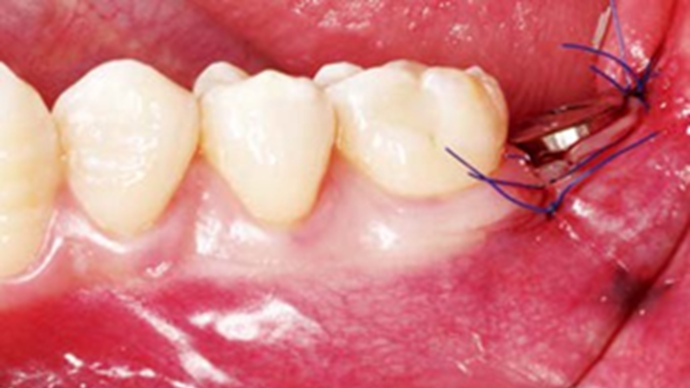

Clinical case: Bone growth in deepest thread of 8.0mm AnyRidge fixture

- Courtesy of Dr. Kwang Bum Park -

AnyRidge, KnifeThread, extraction socket, initial stability, allograft, osseointegration, Dr. Kwang Bum Park, mandibular posterior, single replacement, Mega-Oss

Implant system-AnyRidge, Regeneration-Mega-Oss

Clinical case: Bone filling into the bottom of deepest thread at 8.0mm AnyRidge fixture

AnyRidge, Knifethread ,extraction socket, ,initial stability ,Allograft, ,osseointegratio ,Dr. Kwang Bum Park, , Mandibular, Single replacement, AnyRidge, Mega-oss,